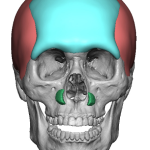

People considering custom jawline implants tend to ask a consistent set of questions. These generally fall into four categories: outcomes, safety, process, and recovery. What are custom jawline implants? Custom jawline implants are patient-specific implants designed from a 3D CT scan of your face. Unlike standard implants, they are digitally created to match your exact Read More…